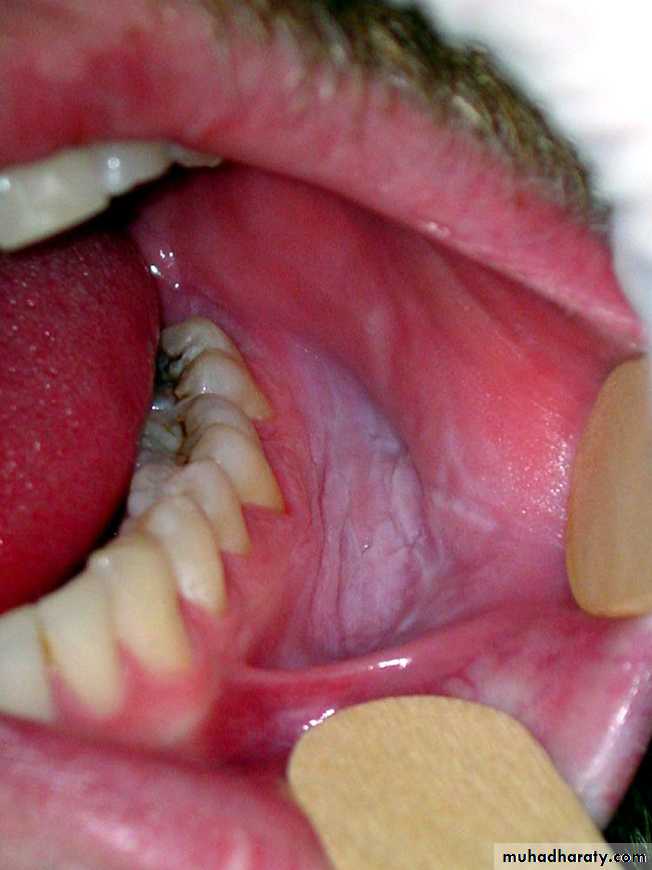

Sublingual keratosis• The term ‘sublingual keratosis’ is applied to white lesions on the floor of mouth

• and ventral surface of the tongue

Sublingual keratosis. This white patch involving the entire ventral tongue and floor of mouth has a uniformly wrinkled appearance. No red areas are associated but the site alone may possibly indicate a high risk of malignant transformation

Sublingual keratosis

Sublingual keratosis. This more irregular white patch is associated with some reddening in the floor of the mouth, which may have a high risk of malignant transformationErythroplakia (Erythroplasia)